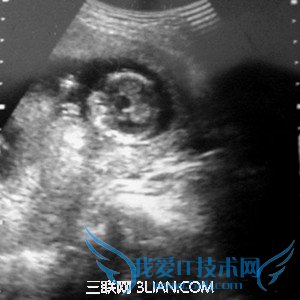

怀孕期间一共是需要做四次B超的,分别是以下几个阶段:

最早的一次B超检查是在怀孕早期,在停经6周之后。除了做一些妇科常规检查之外,还需要通过B超检查来确定宫内妊娠的正常。像宫腔内探查不到任何妊娠现象,而在子宫腔外探到异常的包块,结合一些其他的临床表现和实验室检查结果就可以考虑是不是宫外孕的可能。所以在怀孕早期通过B超能够明确是否是正常的妊娠,以及双胎或者葡萄胎。

16周左右的时候需要做一次B超的,这时候需要了解胎儿的生长发育情况的大概。然后在28周的时候进行B超复查,这时候能够清晰的了解到胎儿组织器官的发育情况,就能够了解是否有畸形,如果有畸形,就要根据医生的建议做相关对策。

最后一次是在36周到预产期之前,这个时候做B超可以明确羊水的多少,胎盘的功能,以及胎儿有没脐带绕颈等。同时B超也可以估量出胎儿的体重,明确胎儿的胎位,这样就能预测孕妇是否能够自然分娩。